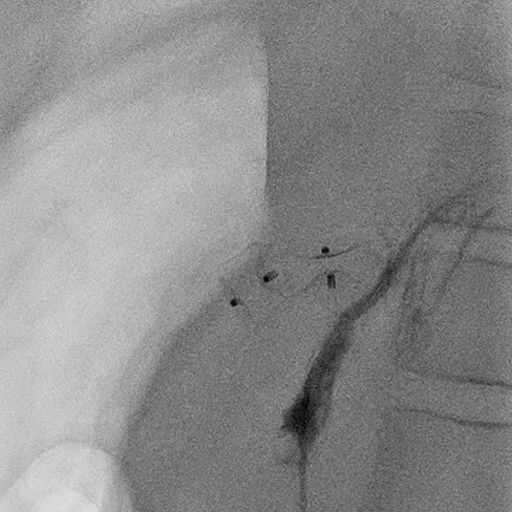

3- jähriger Junge mit stattgehabter Pfortaderthrombose (Verschluss der Pfortader).

Zustand nach Anlage eines Meso-Rex Shunts. Aktuell Größenzunahme der Milz und zunehmende Zeichen des Pfortaderhochdrucks. Sonographisch wurde dann der Verdacht auf eine Stenose (Verengung) der Shunts gestellt. In der Angiographie mit einem Zugang über Milz zeigte sich die vermutete Stenose (Pfeil in Bild A). Es wurde dann ein Stent eingebracht und mittels Ballon dilatiert (B). In der Kontrolle zeigte sich ein gutes Ergebnis mit Beseitigung der Engstelle. Dem Patienten ging es rasch besser.

Abbildungen